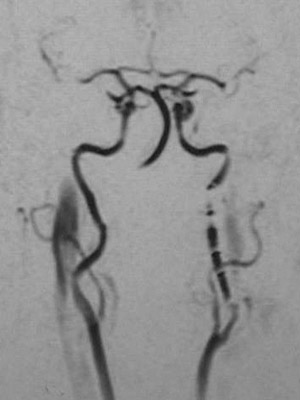

This cerebral angiogram demonstrates fibromuscular dysplasia involving the internal carotid artery on the right, with areas of

beading and narrowing

.